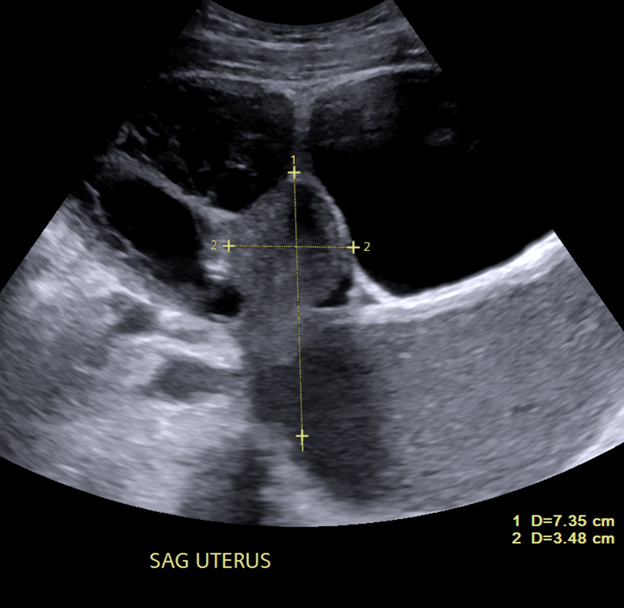

Cases of the Week

Check out our Cases of the Week!